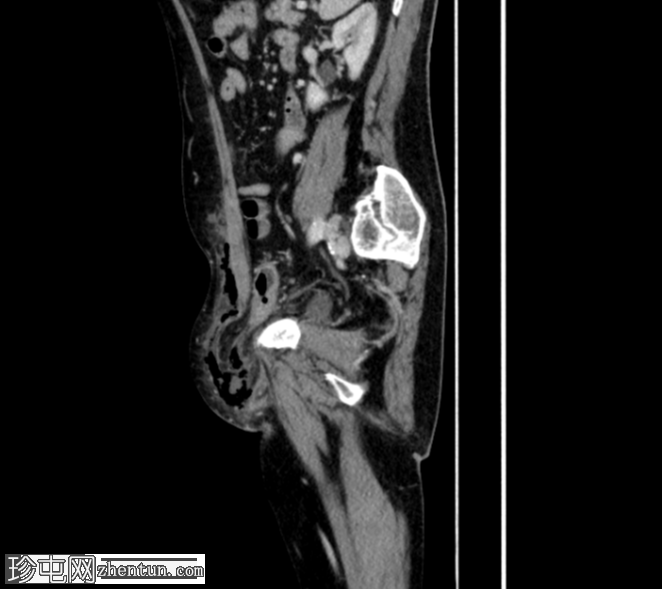

冠状C+门静脉期

疑似乙状结肠憩室炎。左侧直疝,乙状结肠壁一段内有气泡——最有可能是嵌顿疝,憩室穿孔是福尼尔坏疽的病因。

福尼尔坏疽由此沿精索向左半阴囊延伸,并沿腹外斜肌筋膜向头部延伸。